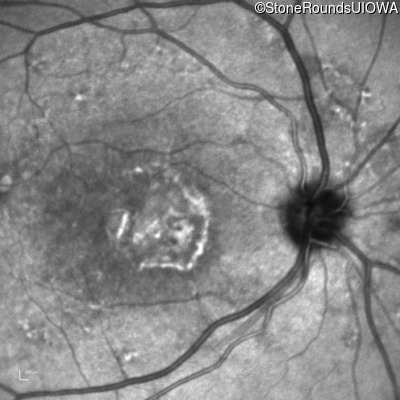

Fluorescein Angiography - Left - 20/20

Exemplar